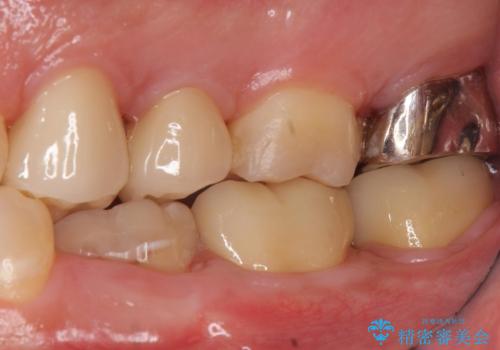

奥歯は十分な歯の高さがなかったため、クラウンをかぶせる前に歯周外科治療で歯の高さを出しています。

歯科に通うようになってから磨き残しの状態も改善されていきました。